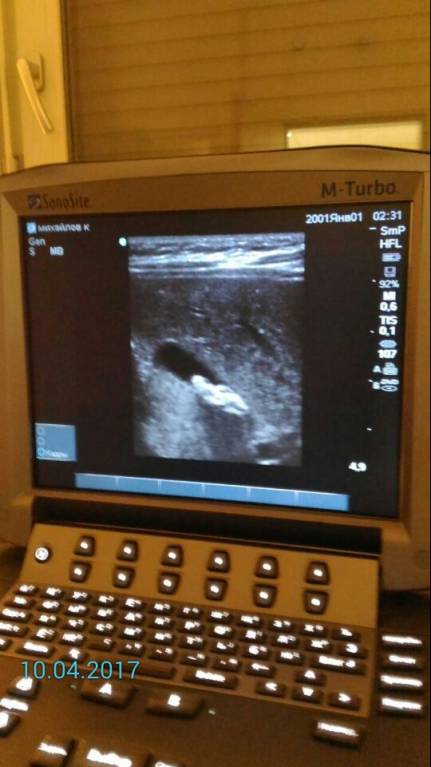

Каждый месяц делаем Узи нам исполнилось 6 месяцев и два месяца нам говорят что у нас уже камни ...

Узи делаем на тощак сначала в лежачем положении потом в вертикальном,и когда поставили вертикально то в желчном все сместилось и тогда Узистка сказала что это 100% камни.

- Камни у малыша с рождения? - ^23485DE77694586C24F923CCF2693CA647F4FDC8A2229AD659^pimgpsh_fullsize_distr.jpg (39.04 КБ) 794 просмотра